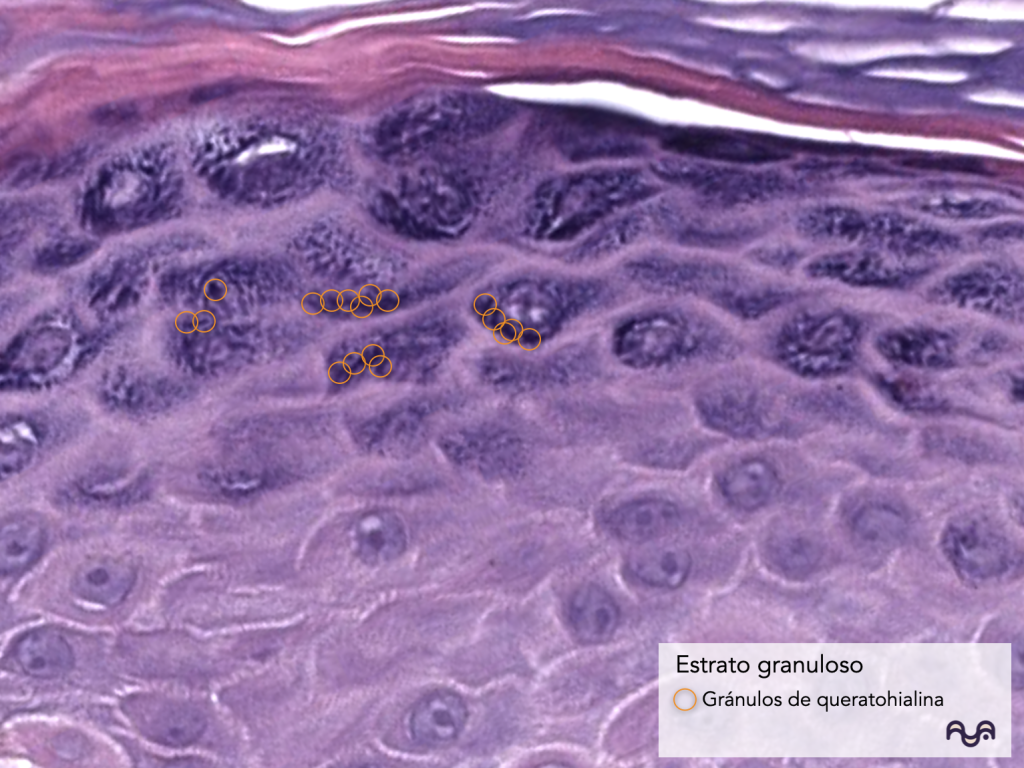

El estrato granuloso se reconoce por la presencia de gránulos basófilos (queratohialina). Yousef 2024

3) Estrato granuloso

Qué es: 1–3 capas de células «horizonalizadas» (variable) con gránulos de queratohialina.

Función: transición crítica hacia la parte de barrera; procesamiento de proteínas (incluida filagrina) y preparación para cornificación. Sandilands 2006

Cómo reconocerlo: “cinturón” basófilo granular.